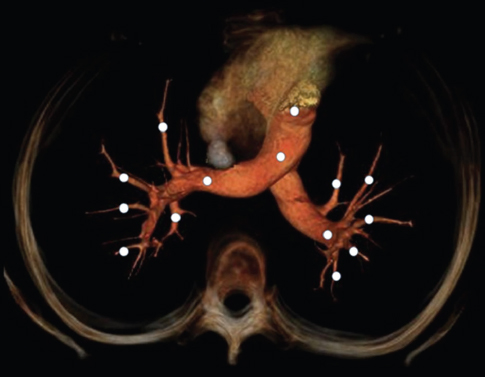

Opacification in HU was measured for all cases in the trans-axial images within the largest circular ROI that would fit within the lumen and exclude the vessel wall. The mean cross-sectional opacification profile of 8 central segments and 11 peripheral pulmonary arteries were measured. In cases where PE was identified, care was taken not to include the emboli within the measurements. Arterial and venous measurements took place at the heart, pulmonary trunk, segmental, and subsegmental pulmonary vasculature and each measurement were no <2 mm in diameter [Figure 1]. The location of the arteries and veins was as follows: Central pulmonary vasculature (trunk, right and left pulmonary arteries, and left superior and inferior pulmonary veins); pulmonary segments; right upper lobe (anterior and posterior), right middle lobe (lateral and medial), right lower lobe (anterior and posterior basal), left upper lobe (apicoposterior and inferior lingular), and left lower lobe (anteromedial basal and posterior basal); and superior vena cava (SVC).

Adjacent to the arterial pathways, the venous measurements were performed in the same axial plane. Image contrast between arteries and veins was expressed as a ratio of HU values (artery/vein) at each anatomical level and denoted as the arteriovenous contrast ratio (AVCR).[18]